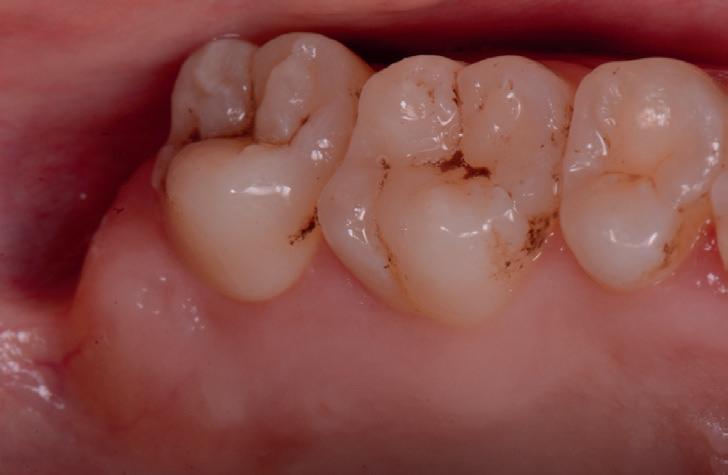

Până la 40% dintre pacienții cu implanturi pot fi afectați de periimplantită după cel puțin 1 an de funcționare. Cel mai bine este ca defectele periimplantare să fie abordate în stadiile incipiente, deoarece cu cât defectul este mai mare, cu atât este mai dificil de tratat. Implanturile dentare trebuie evaluate ca parte a examenului anual al pacientului. Odată detectată BOP, diagnosticul este de mucozită periimplantară impunându-se o serie de recomandări pacientului cu privire la modul de corectare a inflamației, fie prin îmbunătățirea îngrijirii la domiciliu, îndepărtarea biofilmului bacterian și/sau terapia cu laser.

De asemenea, trebuie evaluate anual modificările radiografice. În ședința de inserție a restaurării, se înregistrează o radiografie bitewing standardizată pentru a permite evaluarea anuală a modificărilor osoase din jurul implantului. Remodelarea osului alveolar în primul an este bine documentată și depinde de tipul de implant utilizat; cu toate acestea, nu ar trebui să apară apical de primul filet al implantului. Prin urmare, este importantă abilitatea de a vizualiza filetele implantului pe radiografii. Modificările pierderii osoase de 2 mm sau mai mult după primul an reprezintă un semn de periimplantită. De îndată ce pierderea osoasă este recunoscută, pacientului trebuie să i se recomande terapia imediată pentru a opri procesul de boală.

Defectele intraosoase rezultate din periimplantită tind să fie circumferențiale și să aibă o componentă bacteriană din cauza igienei orale insuficiente, a unei margini coronare defectuoase și/sau a prezenței subgingivale a cimentului. Pentru ca tratamentul regenerativ să aibă succes, trebuie abordați factorii cauzali. Îmbunătățirea igienei orale prin utilizarea aței dentare, restabilirea marginilor sănătoase ale coroanei și îndepărtarea cimentului subgingival sau înlocuirea restaurării cimentate cu una înșurubată ori de câte ori este posibil sunt componente importante ale tratării periimplantitei. Dacă este lăsată netratată, periimplantita poate provoca pierderi osoase extinse și în cele din urmă posibila pierdere a implantului.